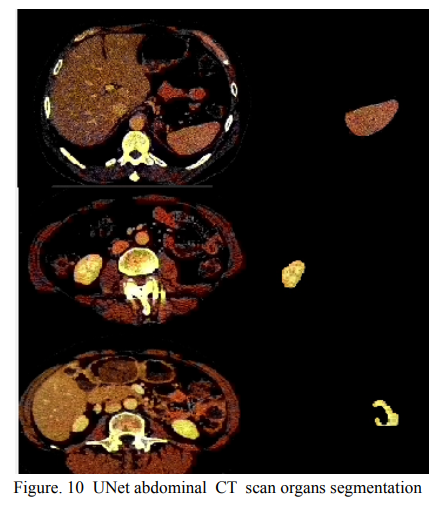

血管分割被广泛用于帮助血管疾病的诊断。使用现有方法重建的血管往往不够准确,无法满足临床使用标准。这是因为三维血管结构非常复杂,并表现出独特的特征,包括稀疏性和各向异性。在本文中,我们提出了一种新型的混合深度神经网络,用于血管分割。我们的网络由两个级联的子网络组成,分别进行初始和细化分割。第二个子网络进一步有两个紧密耦合的组件,一个是传统的基于CNN的U-Net,一个是 graph U-Net。在这两个U型网络之间进行跨网络多尺度特征融合,以有效支持高质量的血管分割。整个级联网络可以从头到尾进行训练。第二个子网络中的graph 是根据血管概率图以及原始CT容积中的外观和语义相似性构建的。为了解决血管的稀疏性和各向异性带来的挑战,较高比例的graph 节点分布在可能包含血管的区域,而较高比例的边缘则是按照潜在的附近血管的方向。广泛的实验表明,我们的深度网络在多个公共和内部数据集上实现了最先进的3D血管分割性能。